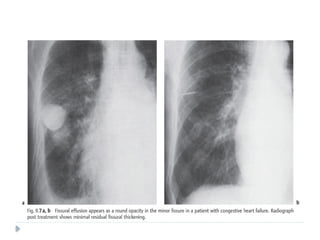

PLEURAL PSEUDOTUMOR

⚫ Is a fluid collection within the lung fissure.

⚫ Most common site : MINOR FISSURE

⚫ Common causes include :

 Congestive heart failure

 Cirrhosis

 Renal insufficiency

⚫ On chest radiographs:

⚫ Classical lenticular or biconvex opacity is seen in

the fissure.

⚫ Usually resolves after therapy with diuretic

agents